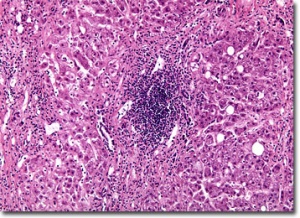

Ваксините за хепатит А са изчерпани от аптечната и складовата мрежа в страната, съобщи за DoctorOnline председателят на Националната аптечна камара Антон Вълев. Причината за това е, че традиционно се поддържа малък брой от тези ваксини, тъй като няма интерес към тях. Сега обаче ситуацията е друга – задава се епидемия от хепатит и това е една от причините за недостига на ваксини. Очаква се аптеките да разполагат с ваксини до 10-ина дни.